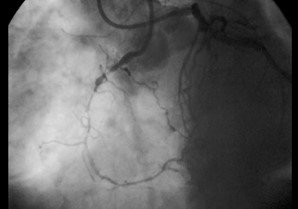

Χρόνια ολική απόφραξη της δεξιάς στεφανιαίας αρτηρίας με παράπλευρη σκιαγράφηση από το σύστημα της αριστερής στεφανιαίας αρτηρίας (διπλή έγχυση)